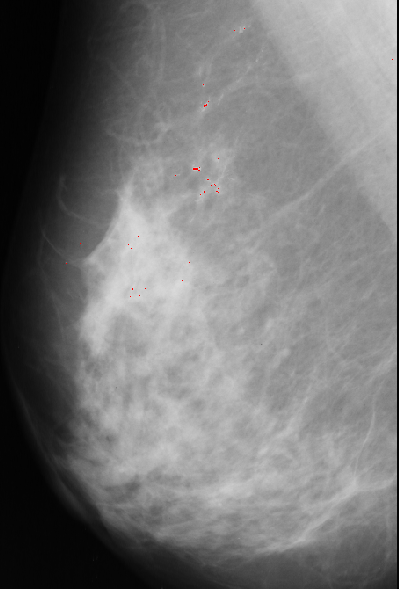

The unsharp filtering only enhances the high-frequency components of the image, thus, has to be followed by a thresholding that will segment the microcalcifications from the breast tissue. This thresholding was done manually and the values for the threshold variable ranged from 170 to 215 in the 4 images.

A result using this approach is presented bellow: